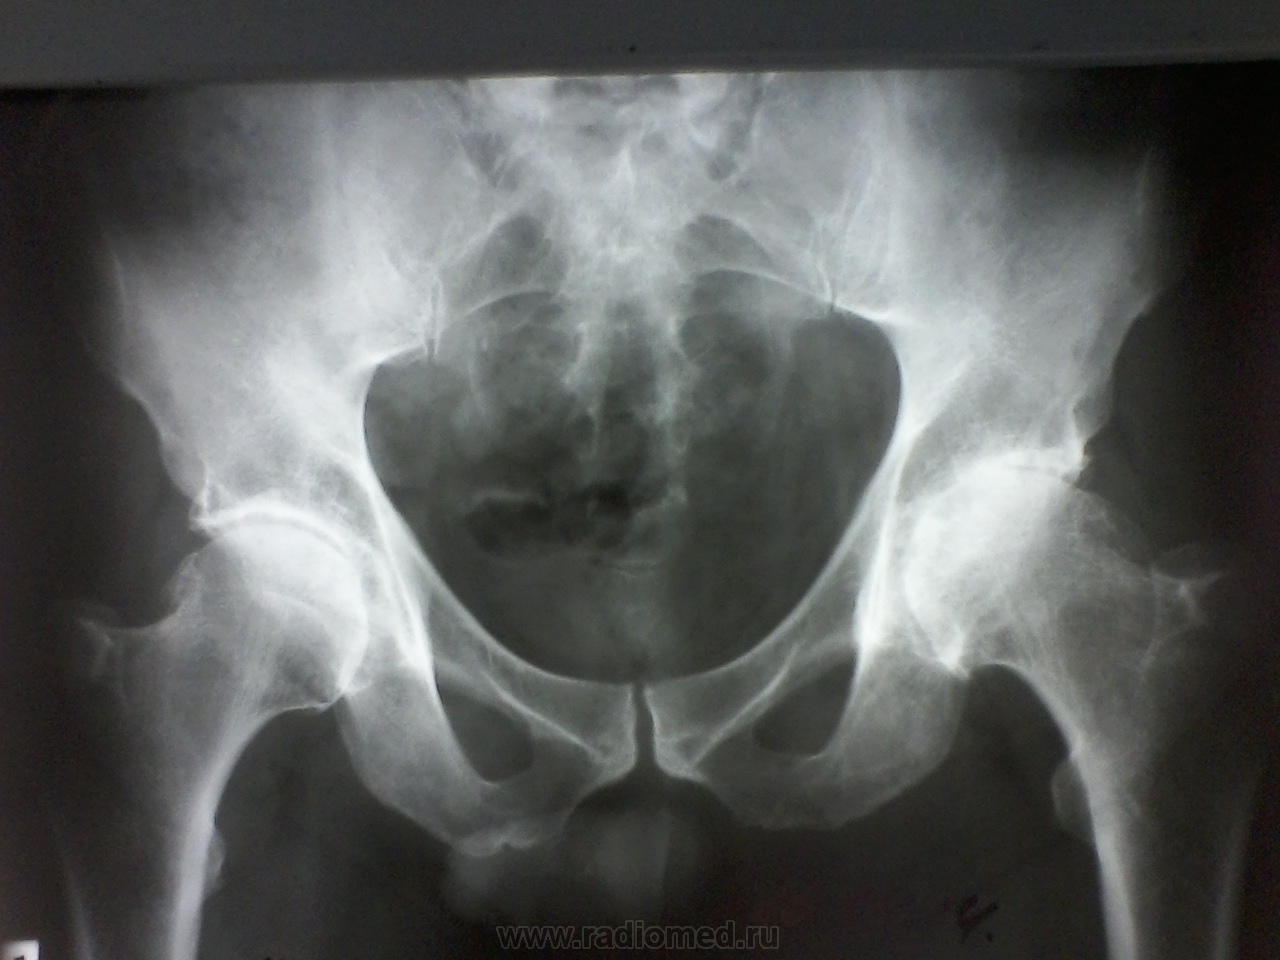

Мужчина лет 50-55, жалобы на боли в т\б суставах около 2 лет, выпоняли Р-гр около года назад, написали коксартроз, отправили лечиться. Сейчас опять боли стали беспокоить. Что скажете, уважаемые коллеги, как описать ?

Артрозоартрит 3-4 ст. по Келлгрену с кистовидной перестройкой сочленяющихся костей бы написал. Бурсит бы добавил, кэп-импиджмент до кучи - а как же, сейчас так всегда.)  А правый сустав как же - двусторонний же процесс - куда-то пропал?

Я наверное к старости слаба глазами стала.Ограничилась бы коксартрозом справа IIст., слева - III ст. (по Косинской), без "-ита", и тем белее без а.некроза.

Что поделать, пишите "асептический некроз". В Азии его пишут: "... Primary OA is the most common diagnosis for THA in studies  from  Europe,  USA,  and Australia,  while  FHN  has  been the most common diagnosis in several studies reported from Asia" - Acta Orthopaedica 2014; 85 (1): 11–17. Ведь, мы же Азия.

Правый сустав теперь я узрел. В нём дела получше. С асептическим некрозом коллеги я не согласен. Но решение Ваше, а моё только мнение,.. никчёмное.)

Не согласен с некрозом я потому, что фонит для него костная ткань совсем слабо, безо всякого склероза и отёка. Разрежение есть её, и предполагаю артритоартроз потому.)

Спасибо всем, написала деф.артроз, асептический некроз не поставила